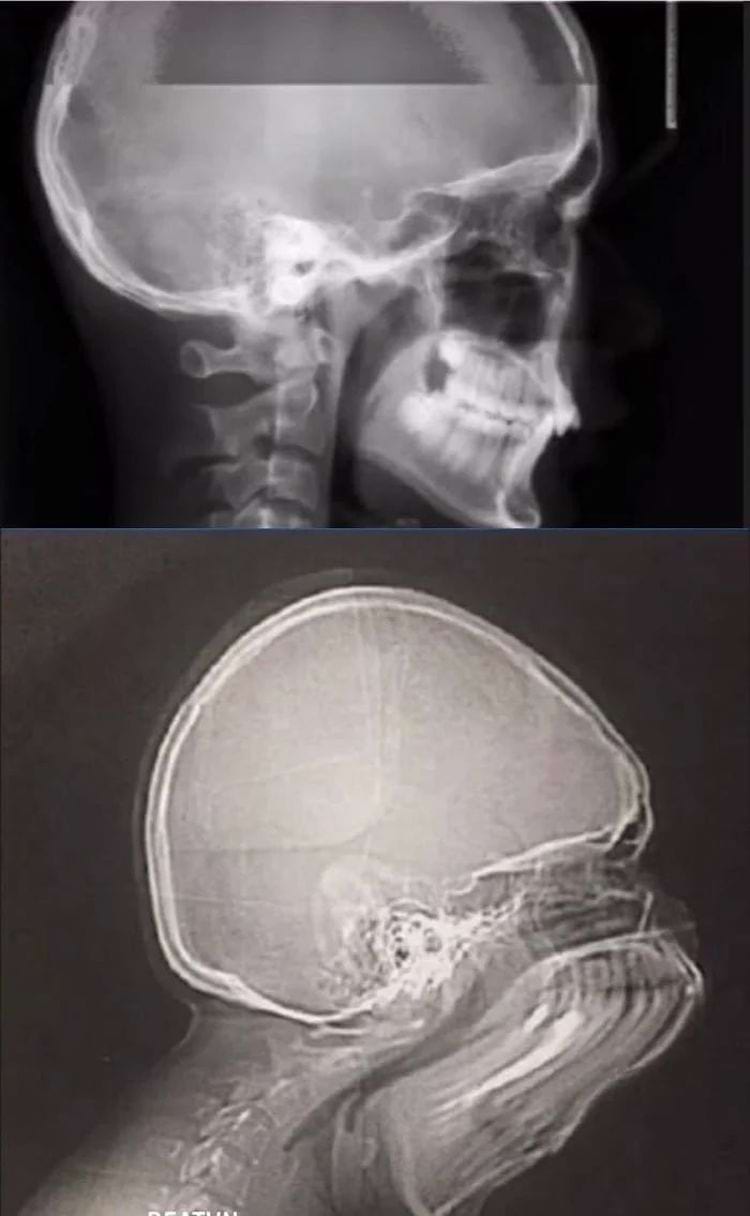

Рентгеновский снимок китаянки, подвергшейся процедуре бинтования ног

Рентгенограмма шеи женщины из племени каян в Бирме справа и обычная шея слева